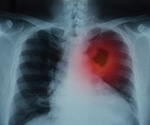

F-actin filaments in a colorectal cancer cell spheroid, captured with light sheet fluorescence microscopy. 70 images were captured through a 90-µm thick sample. b-g) Cross-sectional images taken at 15-µm intervals. Image Credit: Figure reproduced from Prado-López et al. under CC-BY 4.0.